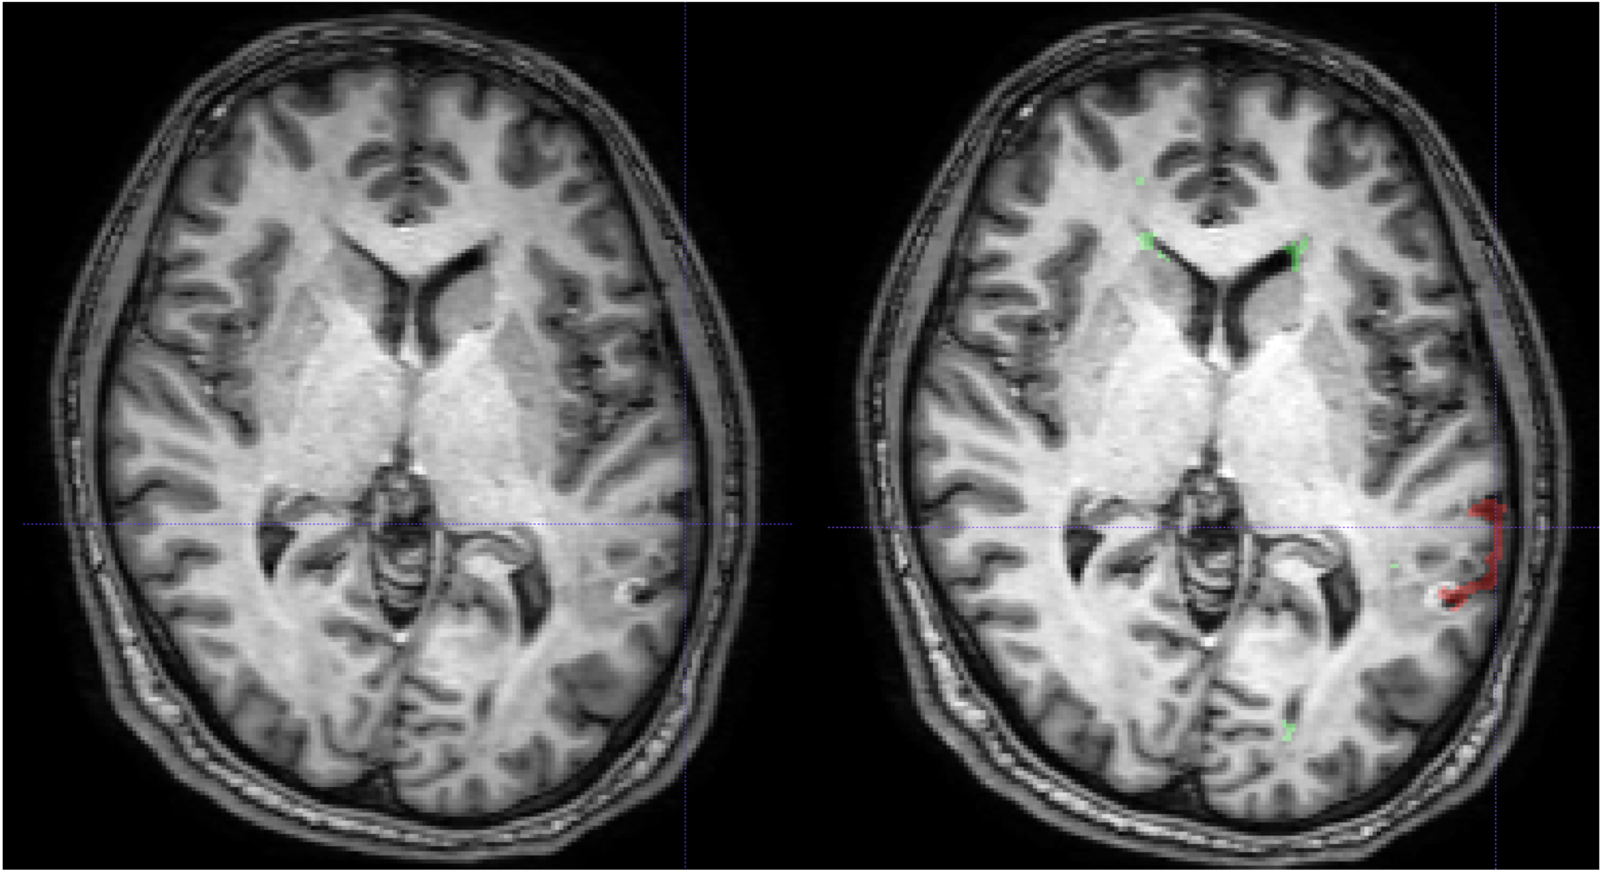

Lesion filling algorithms in MS try to inpaint T1 hypo-intense WM lesion (about 30% of FLAIR-appearing lesions) as Normal-Appearing White Matter (NAWM).

This procedure has NOT been studied before over Cortical Lesions: only ~15% appear as hypo-intense in T1.